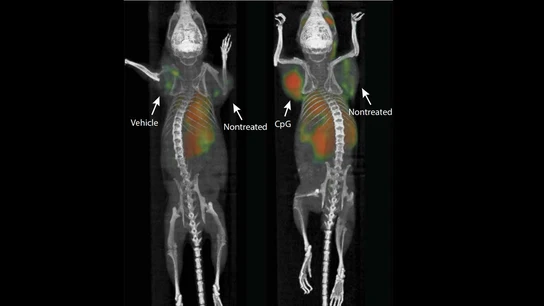

Los científicos han inyectado la vacuna, compuesta por refuerzos inmunes, directamente en los tumores de los ratones y ha tenido efecto. De hecho, ha eliminado hasta la metástasis. Esta inyección ha activado el sistema inmune de los ratones y el cáncer ha remitido.

El experimento se ha hecho en 90 ratones con melanoma y tumores de mama y colon, funcionando con éxito en 87. En los tres restantes, el cáncer apareció de nuevo, sin embargo, tras aplicarles de nuevo la inyección, desapareció.